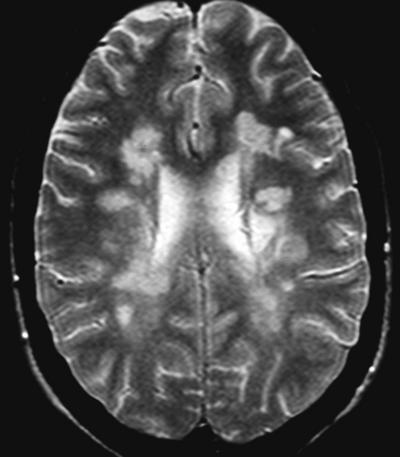

Resonancia Magnética de un paciente con Esclerosis Múltiple